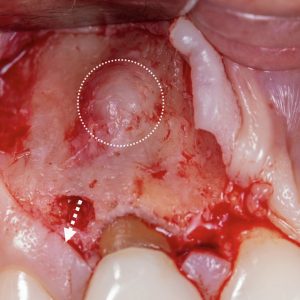

Hard tissue management: osteotomy, apicoectomy, root-end cavity preparation and filling.

Piezoelectric microsurgery.

CBCT planning of surgical procedure.

Hands-on: Microsurgery on anatomical models> anterior teeth

Highlights from past editions